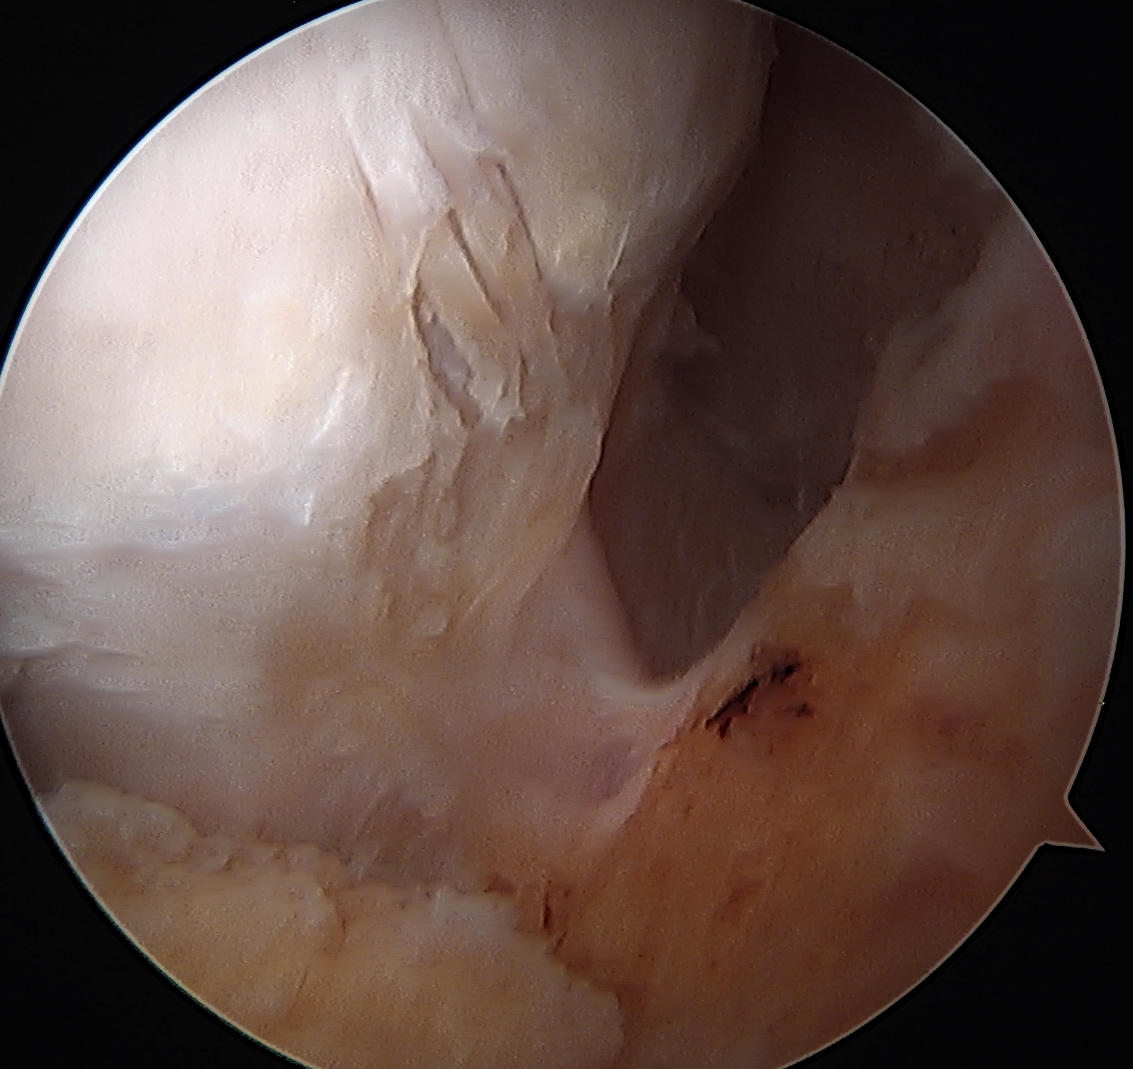

Labral Repair

Assess for Labral Tears

Expose acetabulum

- place proximal capsule suspension sutures

- elevate and protect proximal capsule for later repair

- use cautery to expose acetabulum while not injuring labrum

Acetabular rim trim / Acetabuloplasty

Pincer resection

Os acetabuli resection